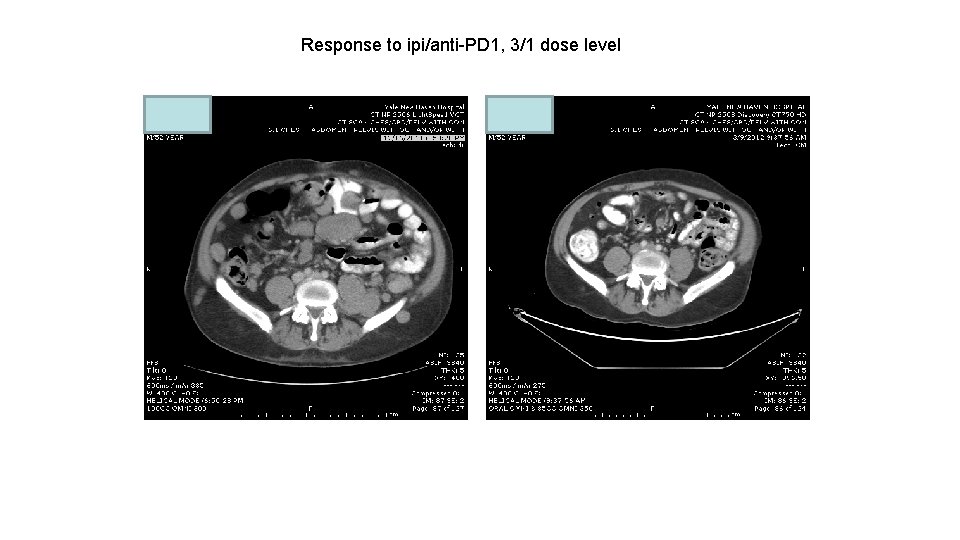

Response to ipi/anti-PD 1, 3/1 dose level